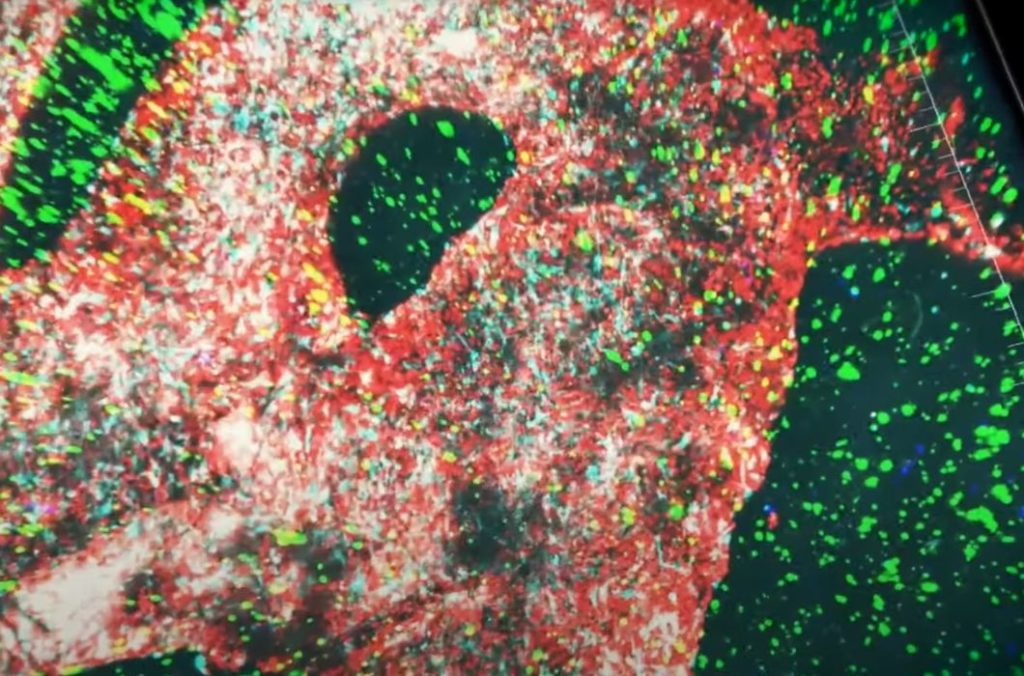

Printing The Glioblastoma

Researchers at Tel Aviv University have 3D printed a working cancer tumor.